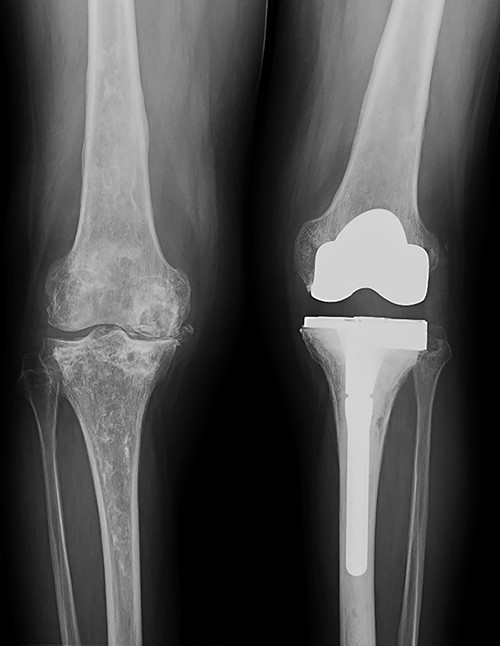

She was referred to our Service to evaluate progressive and disabling pain in both knees. Physical examination revealed bilateral quadriceps atrophy with valgus laxity in the left knee and varus laxity in her right knee. Range of motion (ROM) in both knees was 0°–100°. Standing radiographs showed a pattern of diffuse osteopenia and necrosis (Fig. 1).

Initial both-legs standing radiographs of the knee. It showed a pattern of diffuse osteopenia with areas of sclerosis, lateral extended bone reaction and decreased lateral articular space (Kellgren–Lawrence 3) in the left knee. Bone necrosis with decreased medial articular space (Kellgren–Lawrence 3) were observed in the right knee.